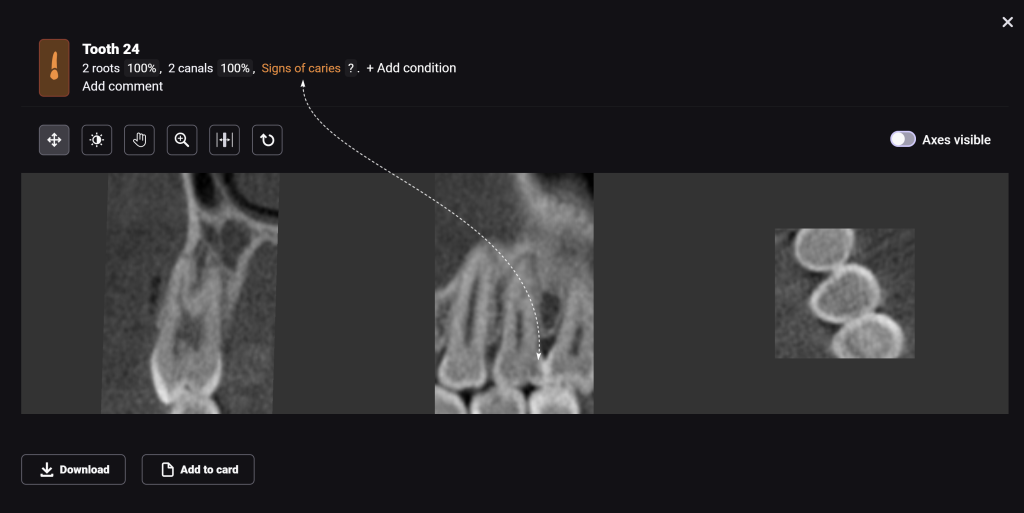

Diagnocat radiological report features an “Conditions with low probability” function. In this mode, teeth marked as “Low probability” are highlighted in yellow. Conditions such as caries and periapical lesions with a probability ranging from 30% to 50%

Additionally, thanks to the “Conditions with low probability,” signs of caries have been detected on the distal surface of tooth 24 (Universal 12)